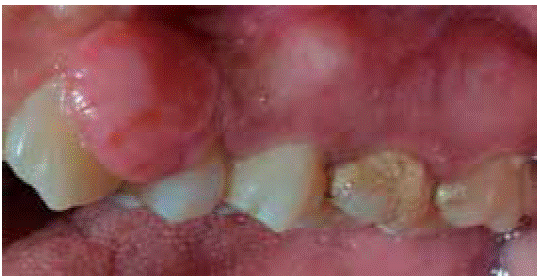

Case 3

A systemically healthy, 29 year old female sought consultation due to a three year old gingival lesion located at the anterior sector of the upper jaw. Patient reported lesion onset during her pregnancy, and progressive lesion growth without presence of pain. Clinical evaluation revealed a soft, mobile, pedicled tumor, approximately measuring 20 X 16 mm located at the level of teeth 23 and The tumor was of a pinkish hue and exhibited keratinization foci (Figure 17). Periodontal assessment revealed periodontal pockets and a 78% oral hygiene index (O'Leary). Radiographic examination showed interproximal calculus in the gingival lesion area (Figure 18).

Presumptive diagnosis: pyogenic granuloma.

Treatment: oral hygiene instruction was administered, followed by root scaling and planing, after which an excisional biopsy of the lesion was conducted (Figure 19) as well as a gingivoplasty procedure. Moreover, support periodontal therapy was recommended with periodontal maintenance sessions every three months during the first year.